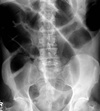

Intracapsular NOF

Subcapital fracture (intracapsular)